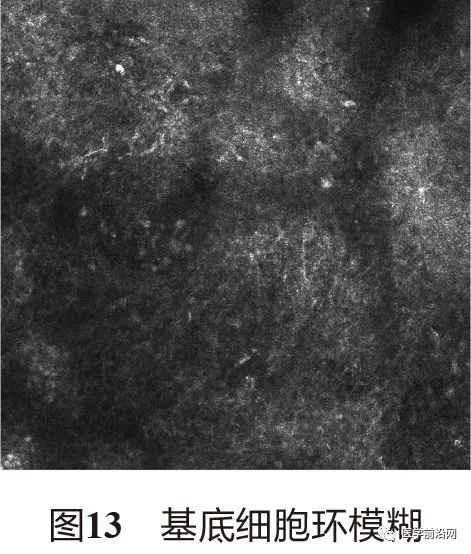

3.2 光泽苔藓 表皮萎缩变薄,真皮乳头增宽(图12),基底细胞环模糊(图13),中央可见不等量高折光的噬黑素细胞及其他较为致密的中低折光混合炎性细胞浸润(图14)。